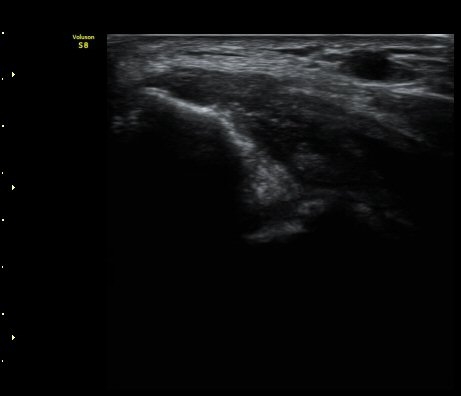

¼Ò½Ç ¹× Àü¹ÝÀûÀÎ Àú¿¡ÄÚ ºÎÁ¾ÀÌ °üÂûµÈ´Ù(±×¸² 1, 2, 3). ±¼°î°Ç ÀϺδ Á¤»óÀûÀÎ °í¿¡ÄÚ

¼¶À¯ ¾ç»óÀ¸·Î °üÂûµÈ´Ù(±×¸² 4). ÈûÁ٠Ⱦ´Ü¸é °Ë»ç¿¡¼­µµ °Ç³» ¿¬°á¼º ¼Ò½Ç°ú Àú¿¡ÄÚ

º¯È­°¡ °üÂûµÈ´Ù(±×¸² 5).  ÃÊÀ½ÆÄÀ¯µµÇÏ ÁÖ»ç ½Ã ÁÖ»ç¾×ÀÌ °Ç³»¿¡¼­ ÀÚÀ¯·Ó°Ô ÆÛÁ®¼­